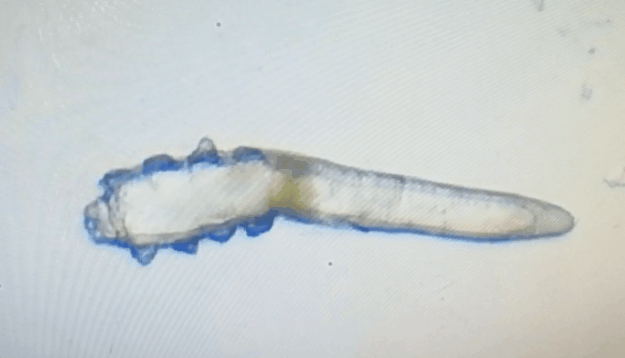

廈門眼科中心眼表及角膜病專家商旭敏博士指出:蠕形螨中的毛囊蠕形螨和皮脂蠕形螨可寄居于人體。在眼部,毛囊蠕形螨常寄居于睫毛囊,而皮脂蠕形螨多寄居于眼瞼皮膚的皮脂腺和瞼板腺。蠕形螨瞼緣炎是蠕形螨感染瞼緣所致的慢性炎性反應(yīng)性疾病,主要累及瞼緣皮膚、睫毛囊和腺體以及瞼板腺,以眼癢、眼異物感、眼干、瞼緣充血、鱗屑及睫毛根部袖套狀分泌物等為典型臨床表現(xiàn),嚴(yán)重者可引起結(jié)膜及角膜并發(fā)癥,該病可能具有一定的傳染性。

蠕形螨的危害不容小覷!??!

蠕形螨會(huì)引起睫毛異常,引發(fā)瞼緣炎性反應(yīng),瞼板腺堵塞,引起結(jié)膜炎、角膜炎等并發(fā)癥,嚴(yán)重的話將發(fā)生角膜穿孔致視力損傷甚至失明。